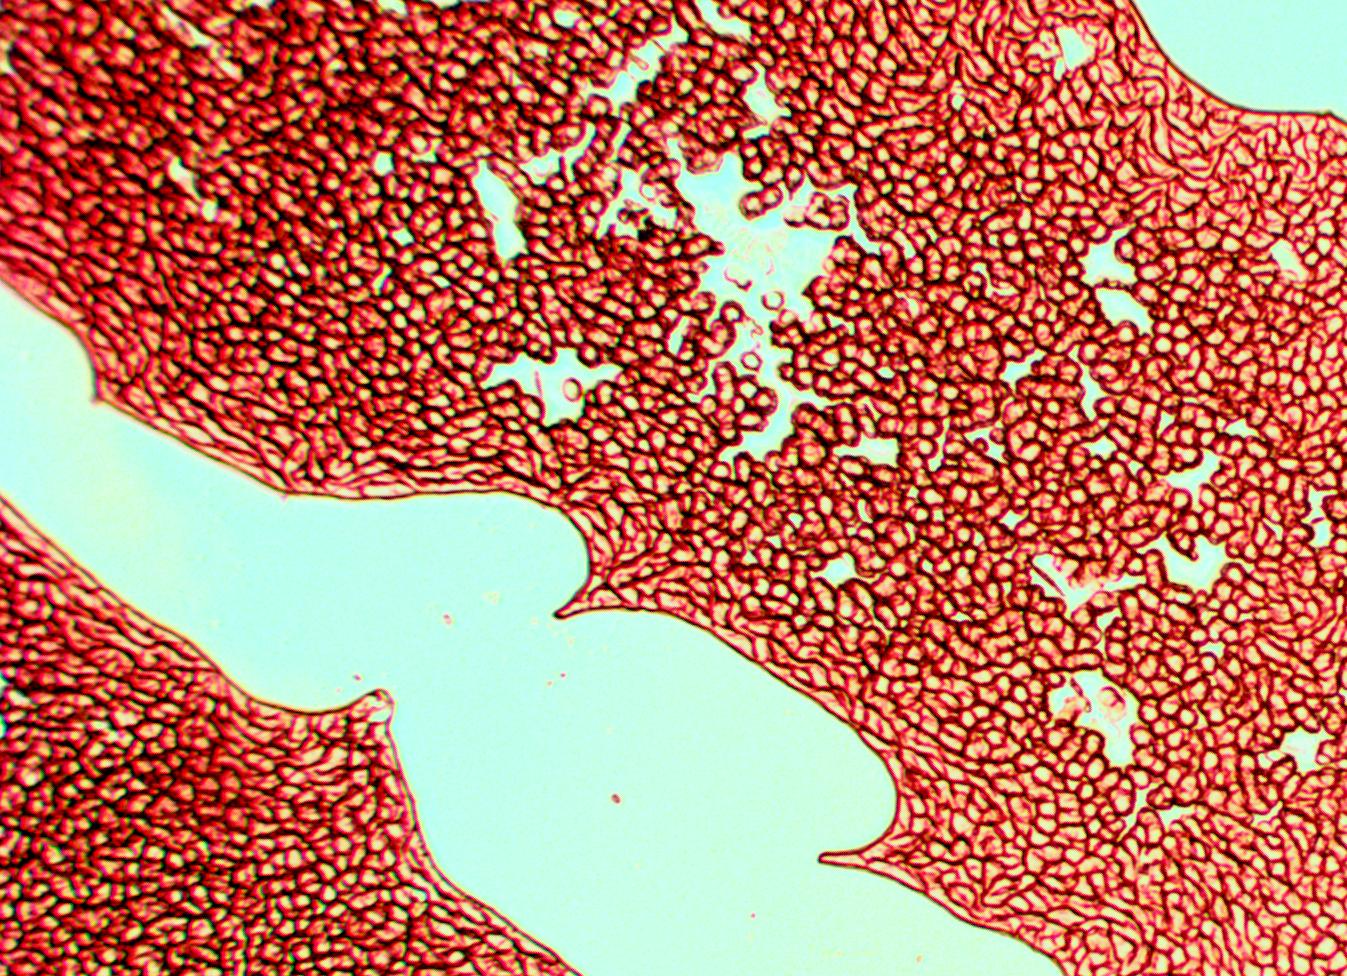

Эритроциты – красные тельца дисковидной формы, которые транспортируют кислород по телу человека. Диаметр – 7–10 мкм. Цвет этих клеток обусловлен содержанием в них гемоглобина – специального вещества, которое позволяет им переносить молекулы кислорода. Эти клетки наиболее многочисленны, поэтому, рассматривая кровь человека под микроскопом, их вы увидите в первую очередь.

| Кровь человека под микроскопом, 150x |